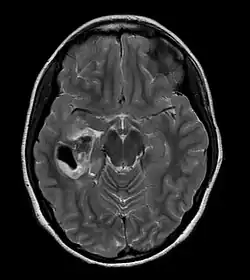

| CT scan of a brain with pleomorphic xanthoastrocytoma. The classic radiographic appearance is one of a superficially situated tumor, here a mural nodule, associated with an underlying cyst. |

Pleomorphic xanthoastrocytoma usually develops within the supratentorial region (the area of the brain located above the tentorium cerebelli). It is generally located superficially (in the uppermost sections) in the cerebral hemispheres and involves the leptomeninges. It rarely arises from the spinal cord.

These tumors are formed through the mitosis of astrocytes. They are found in the area of the temples, in the brain's frontal lobe or on top of the parietal lobe. In about 20% of cases, tumors exist in more than one lobe.